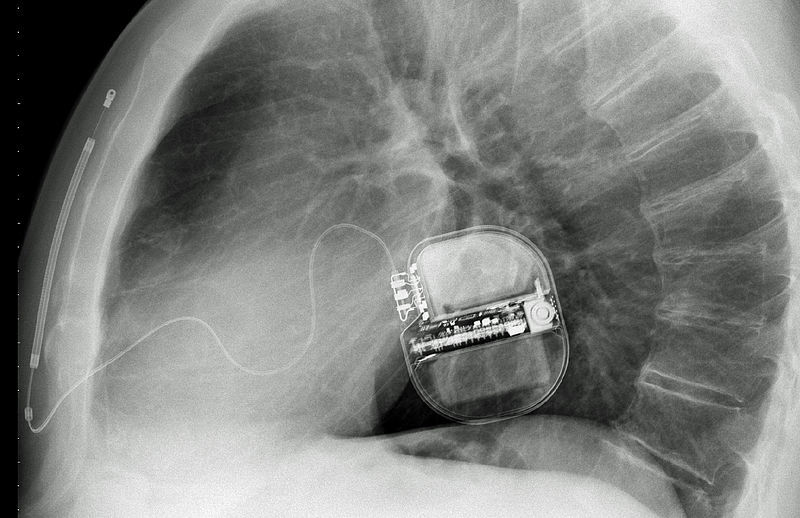

ICDs are used to save the lives of patients who suffer sudden cardiac death. ICDs deliver a shock that restores a normal heart rhythm when other parts of the heart cause it to beat in an erratic way. The device often errs when it mistakenly interprets a different rhythm issue as ventricular arrhythmia, such as abnormal rhythms in the heart usually started within the lower chambers of the heart.